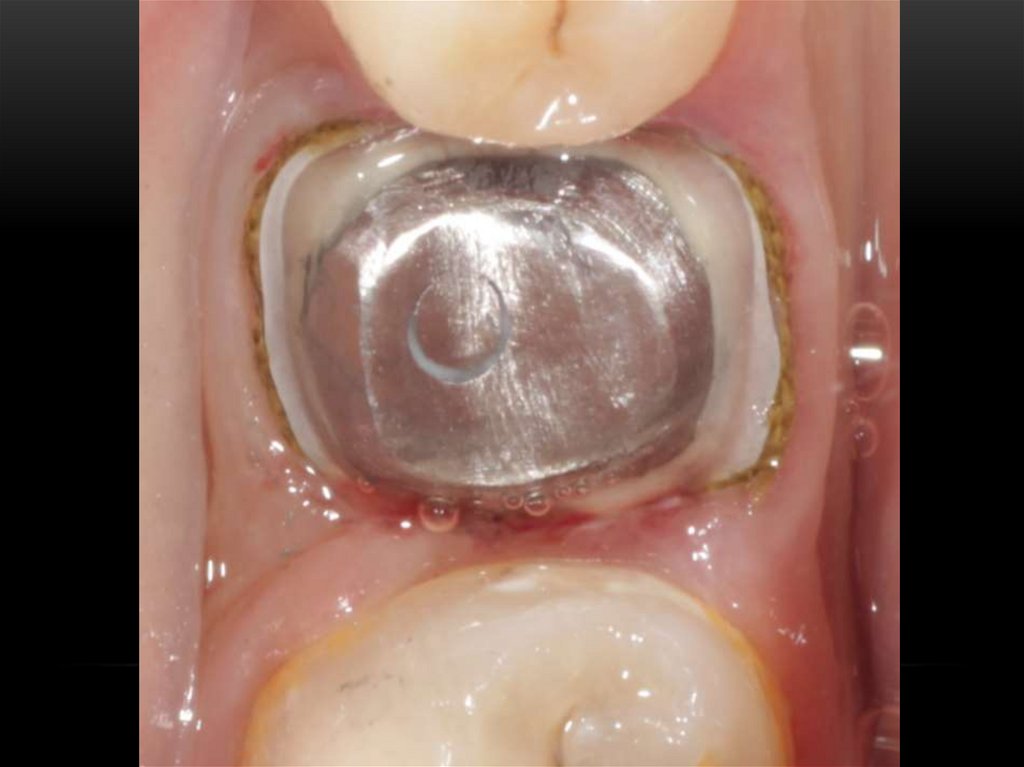

Лечение корневых каналов